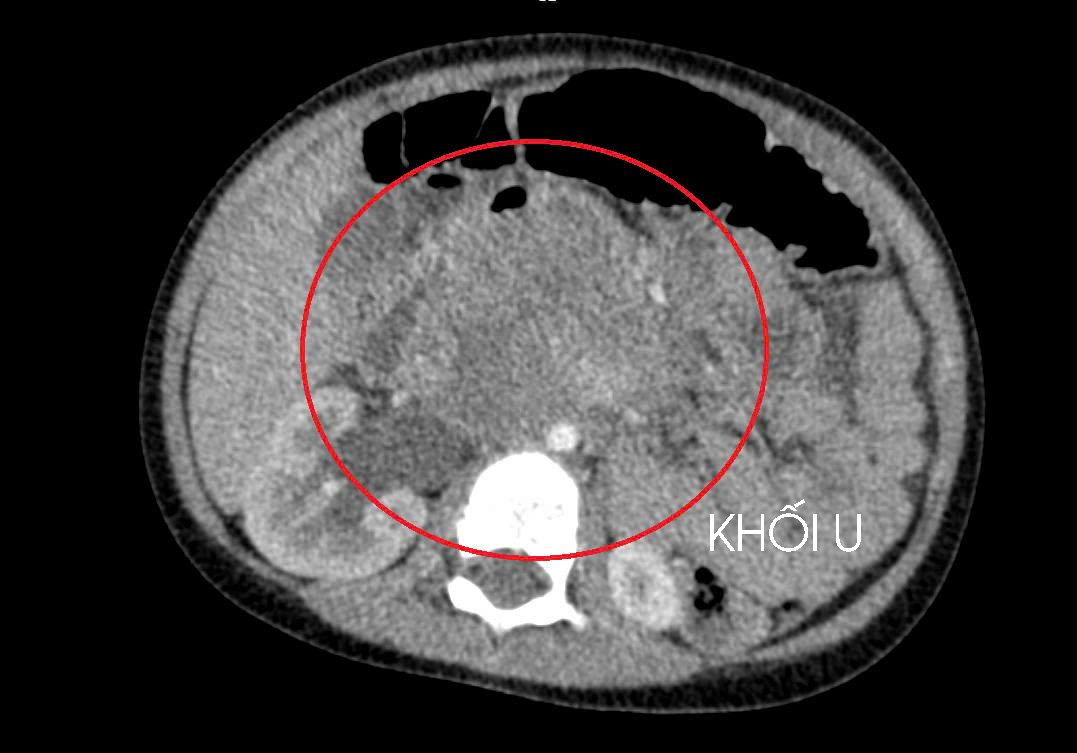

A large tumor, compressing the kidney and metastasized. Photo: _Hospital provided_

On 10/1, doctors at Hung Vuong General Hospital reported a three-year-old boy was diagnosed with metastatic testicular cancer, which had spread to his liver and lungs. The diagnosis followed an extended period of abdominal pain, during which his family, residing in a remote area, faced challenges accessing medical care and screening. By the time he was admitted, a large tumor was compressing his kidney. The cancer originated from an undescended testicle, which had remained in his abdominal cavity since birth and developed silently without clear symptoms during his early years.